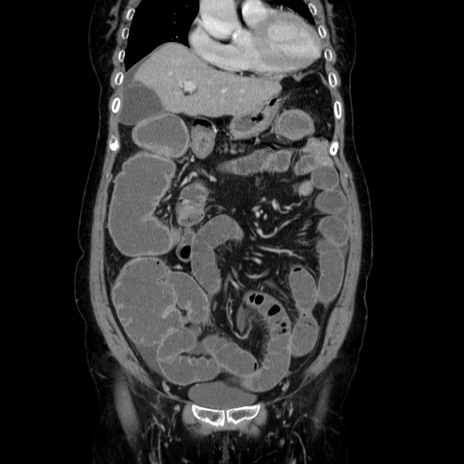

横断像

【症例】70歳代女性

【主訴】お腹が張る

【現病歴】1週間くらい前から腹部膨満の自覚あり。昨日夜から増悪したため、本日救急外来受診。

【身体所見】意識清明、BT 36.5℃、BP 165/106mmHg、HR 80bpm、SpO2 98%、腹部:膨満、軟、自発痛・圧痛なし、触診にて不快感あり、腸蠕動音:減弱

【データ】WBC 12600、CRP 1.04